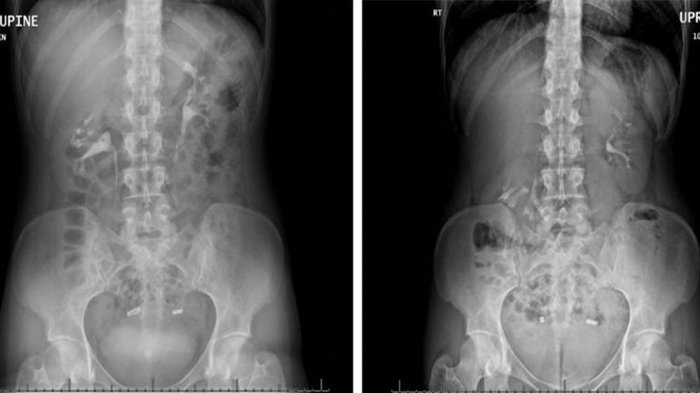

Hasil CT Scan seorang perempuan yang ginjalnya turun sampai panggul. Hasil CT Scan kiri, diambil saat perempuan itu berbaring dan terlihat letak ginjalnya normal. Hasil CT Scan kanan, diambil saat berdiri da menunjukkan ginjal kanannya (terlihat di sebelah kiri dalam hasil CT Scan) jatuh ke panggul. Ginjal kiri (terlihat di sebelah kanan dalam pemindaian) berada di bawah tulang rusuk.

Menurut hasil CT scan, ginjal kanannya turun sampai 6 sentimeter atau melewati dua ruas tulang belakang saat berdiri.